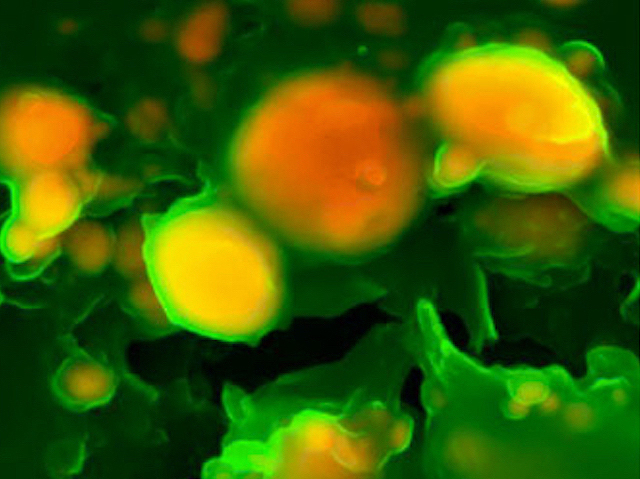

Clogging the Tubes

Extracellular vesicles – packaged secretions from cells – trigger vessel-blocking deposits

Cardiovascular disease – problems with the heart and blood vessels – is the biggest leading cause of death worldwide. Many of these issues are caused by fatty buildups called atherosclerotic plaques, which clog the arteries and lead to heart attacks, strokes and other serious health effects. It’s now known that plaques start from collections of tiny blobs called microcalcifications, seen here (orange) in the carotid artery (tissue in green) that runs up the neck and supplies blood to the brain, but it’s not clear what triggers the microcalcifications to form in the first place. Researchers have discovered that little packets of molecules released from cells (extracellular vesicles, EVs), seem to play an important role in kick-starting the process. EVs and microcalcifications have been seen in other diseases including cancer and dementia, so knowing more about how they’re made, what they contain and how they function could be very important for preventing and treating many conditions.